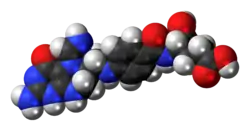

3D model (JSmol) |